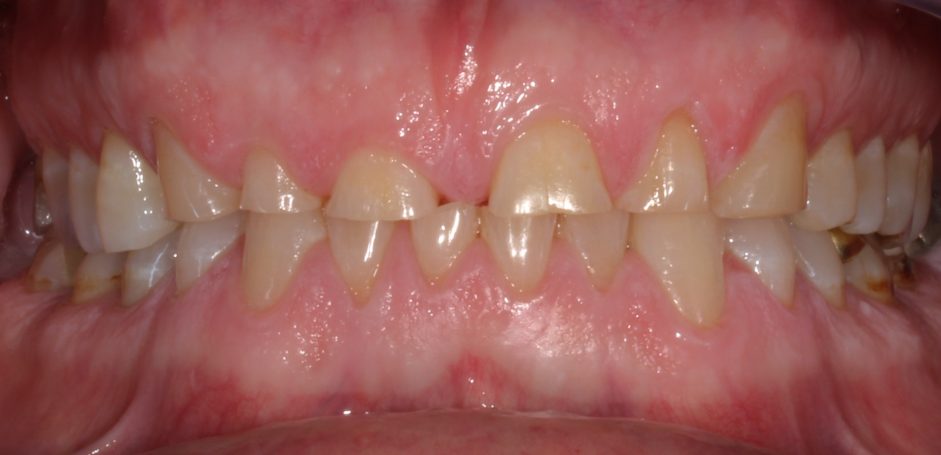

Teleskopierende Oberkieferbrücke mit Vorher- und Nachher-Situation des Patienten.

Teleskopierende Oberkieferbrücke. Wie die eigenen Zähne, aber einfach zu reinigen.